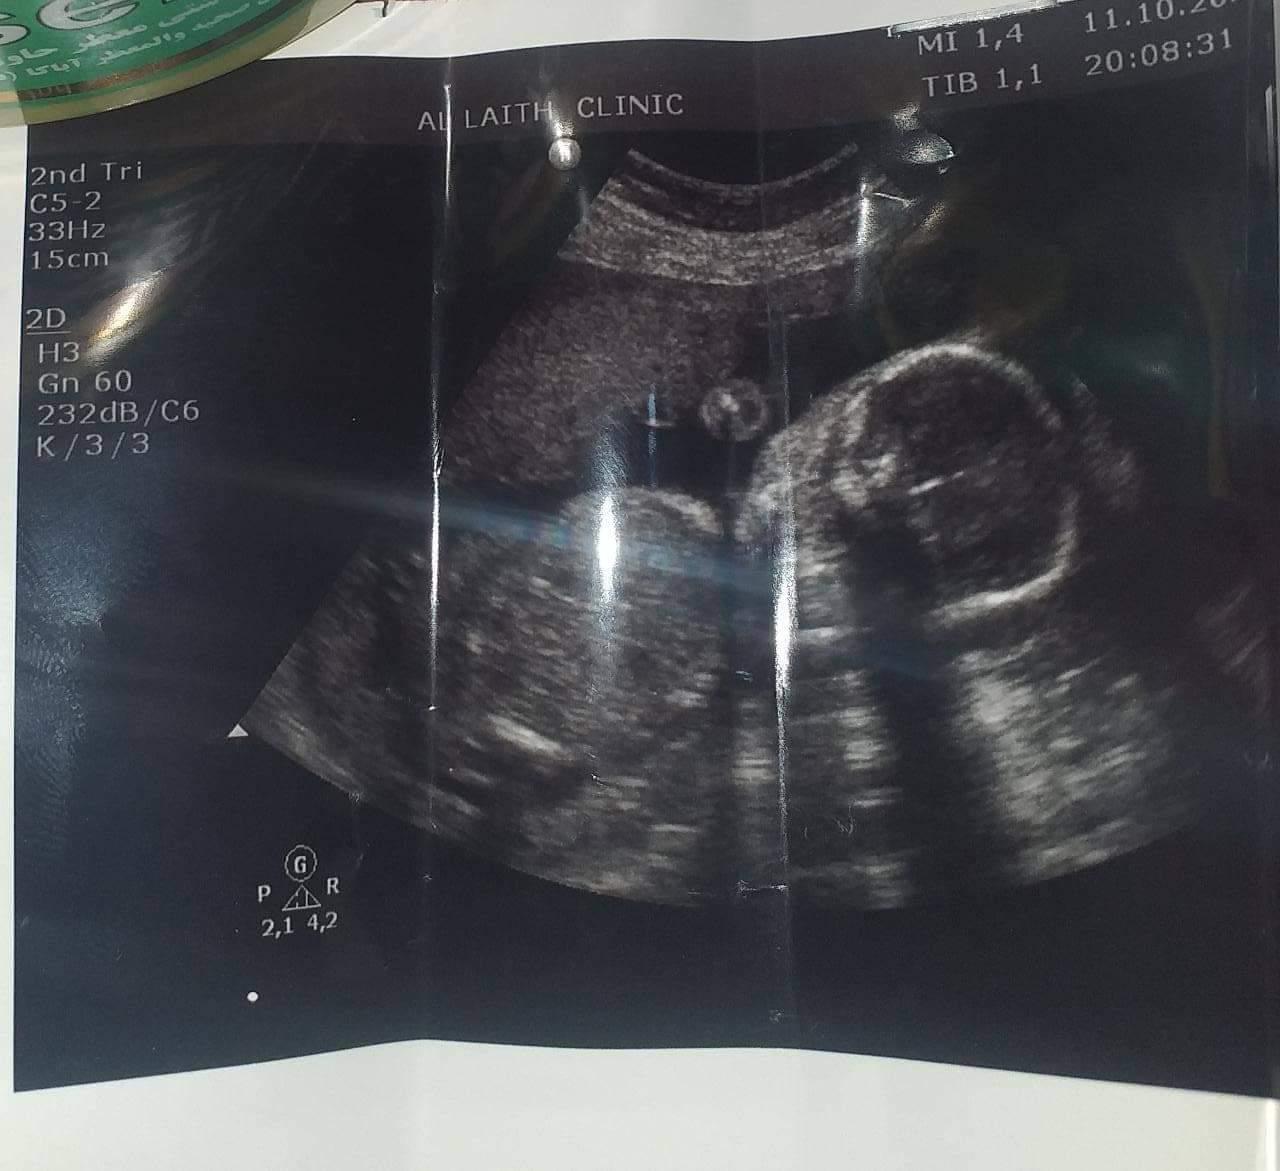

العراق - أعلنت الدكتورة الإستشارية أزهار العضب إنها بعد التوكل على الله وبفضلٍ منه أُجريتُ العديد من عمليات الناظور البطني  لمئات الأعداد من المريضات اللواتي  كن يعانين من مشكلة التأخير في الحمل لا سيما أن أعداد مرضى العقم عند النساء قد تزايد بشكل  مخيف في السنوات الأخيرة .

وبفضل الله قد انهيتُ هذا المعاناة وكنت سبب في تحقيق حلم تكوين العائلة وإعلان شبه نهائي نهاية العقم أو تأخير الحمل عند النساء حيث بلغ العدد الإجمالي للنساء اللواتي أصحبنا حوامل أكثر من ١٠٠ امرأة